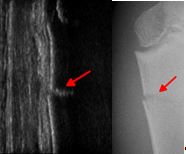

In vielen Fällen biete die Ultraschalldiagnostik eine Alternative zum Röntgenbild. So könnten sehr häufig vorkommende Handgelenksbrüche in neun vor zehn Fällen rein sonografisch diagnostiziert und kontrolliert werden. Bei Ellenbogenbrüchen ließen sich 70 Prozent und an der Schulter sogar drei Viertel der Röntgenbilder einsparen, so Ackermann. „Die Sonografie basiert auf ungefährlichen Schallwellen und hat auch bei intensiver Anwendung keine gesundheitsschädlichen Nebenwirkungen“, ergänzt der Experte.

In den letzten 15 Jahren haben wissenschaftliche Arbeitsgruppen weltweit mehrere tausend Patienten untersucht und die Sonografie mit der Röntgendiagnostik verglichen. „Dadurch wurden sichere Anwendungsbereiche definiert und standardisierte Vorgehensweisen entwickelt“, erklärt Ackermann und betont: „Wir befürworten ausdrücklich, dass Ärzte im Sinne der Patienten – gerade der Kinder – den Ultraschall als schonendes Verfahren hier viel häufiger einsetzen.“ Dies gelte umso mehr, als die erforderlichen Geräte bereits flächendeckend in Kliniken und Arztpraxen vorhanden sind. Die notwendige Qualifikation können Ärzte bei der DEGUM in Intensivkursen erwerben.